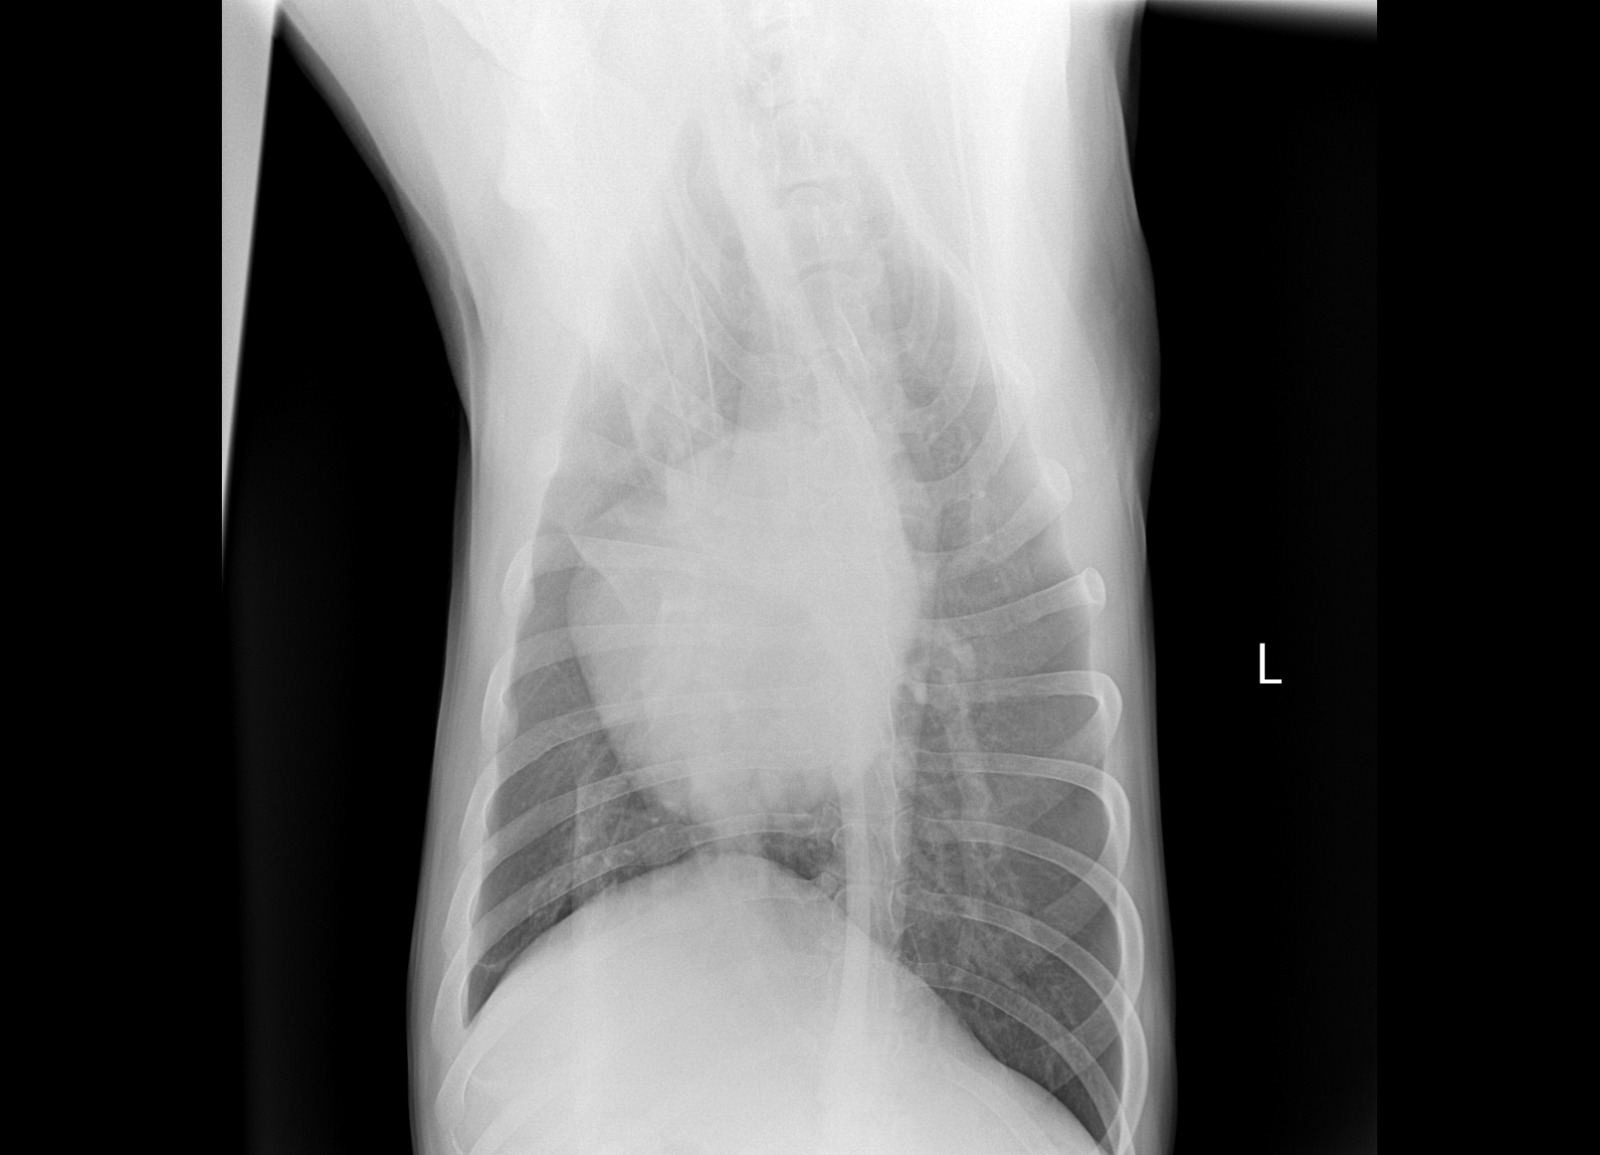

Рентген

Интересно, а изменения в бронхах на рентгене от диро или результат хронического бронхита?